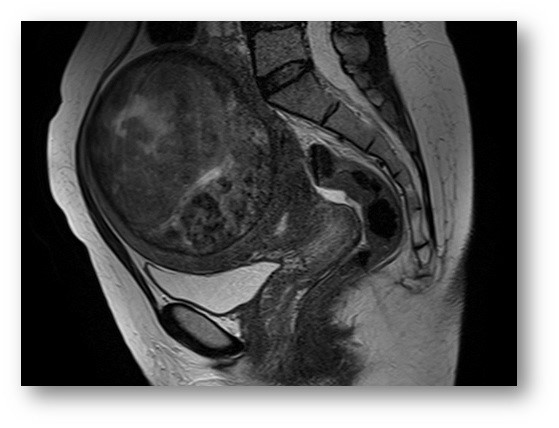

КТ-исследование абсцесса малого таза: Визуализация и диагностика

Раздел: Фотоальбом решений